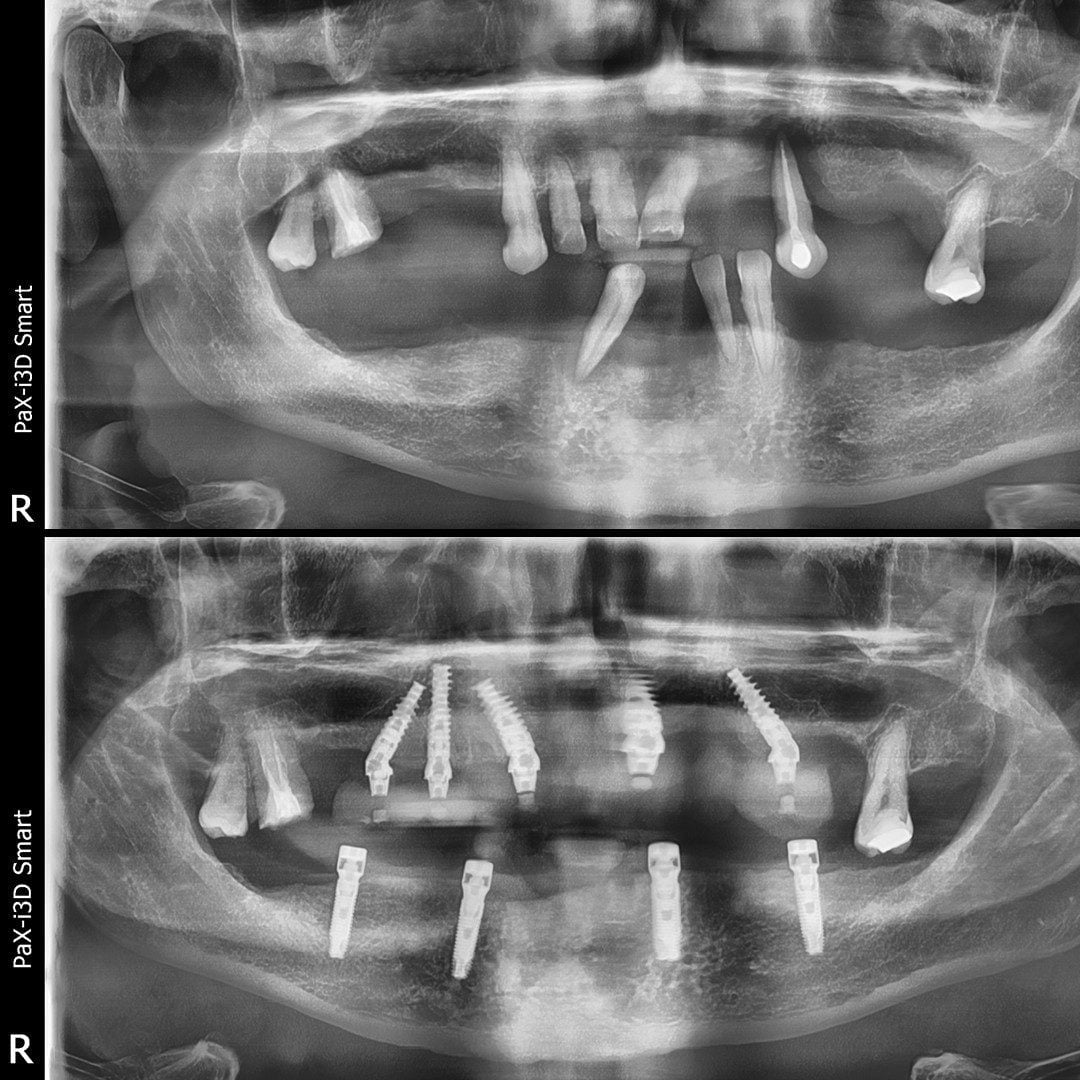

Dinți Ficși în 8-24 de ore pe implanturi dentare cu tehnica All-on-4/All-on-6 este cea mai eficientă și rapidă metodă de restaurare totală a danturii.

- Intervenția chirurgicală

Peste 4000 Implanturi dentare inserate